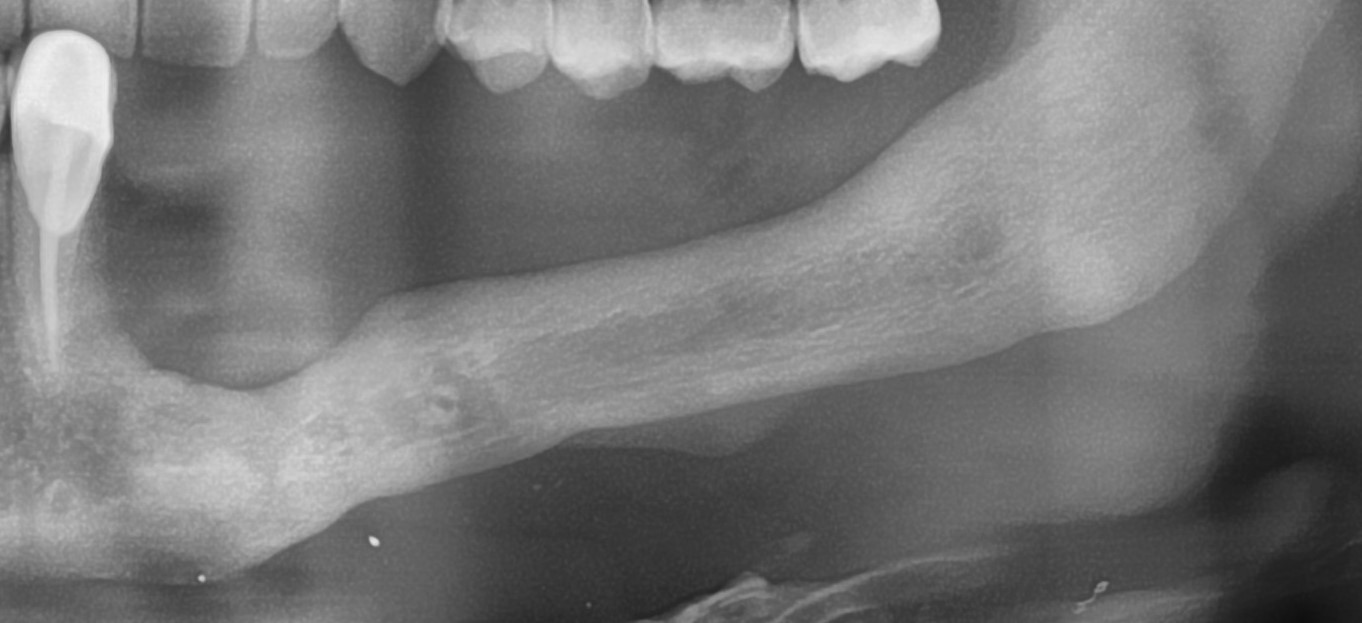

На первое место я бы поставил форму дефекта. Немного забегая вперед (а это будет темой следующей статьи), выбор метода наращивания костной ткани зависит, в основном, от двух параметров: биотипа кости и формы атрофического дефекта. Подробнее об этом я написал здесь>>. В общих чертах, некоторые случаи потери кости настолько сложные для наращивания, что сопоставляя стоимость, целесообразность и возможные риски, лучше отказаться от остеопластики в пользу какой-нибудь методики нетрадиционной сексуальной имплантации, типа «всё на четырёх», ультракоротких или базальных имплантов. Да-да, вы не ослышались! Базальные имплантаты — вполне себе метод, если отобрать их у доктора Иде, если использовать его по показаниям.

Как, например, в этом случае. Правда, это Ankylos: